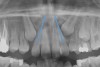

Dental impactions may occur for several reasons. A common occurrence is insufficient arch length leading to crowding. Another potential reason is early loss of primary teeth without proper space maintenance, allowing the permanent dentition to drift mesially and block out the primary tooth's successor. Maxillary canines are the most commonly impacted teeth besides third molars. These teeth have the longest path of eruption, are one of the last teeth to erupt into the mouth, easily become blocked out due to crowding or trauma history, and have a genetic component to being palatally impacted.5,6 Early signs of canine impaction may be severe crowding and the permanent lateral incisor crowns flaring distally. The crown of the impacted canine, in essence, is applying pressure to the roots of the lateral incisors in these instances (Figure 3 and Figure 4).

Fig 4. Impacted canine, radiographic signs. Lateral incisor crown distal flaring is apparent.

Figure 4